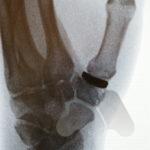

Carpal tunnel syndrome affects the median nerve that travels through a space that connects the forearm and hand at the front of the wrist. Pressure on the nerve, from many possible causes, can lead to a slowing of the electrical signals that supply sensation to the thumb, index and middle finger. It can lead to tingling and numbness in these fingers or the whole hand and can often be worse at night time.